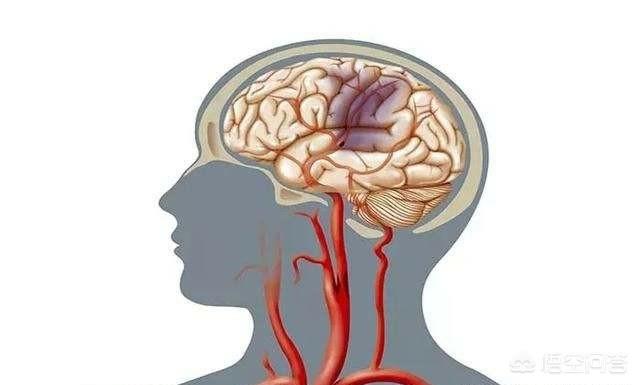

脳梗塞のような重篤な血液供給不足は、脳を供給している血管の1本が完全に閉塞し、その血管が供給している部分の脳細胞が死滅し、機能が完全に失われることである。脳梗塞になると、片麻痺、片目の失明、体の片側の感覚が完全になくなるなどの深刻な症状が現れる。

- 脳梗塞

第10に、長期にわたる脳血液の供給不足は、脳梗塞、海綿体梗塞、さらには他の脳血管疾患を引き起こす可能性があり、これはより深刻な反応である。

脳への血液供給が不足した状態が長期間続いたり、治療が適時に行われなかったりすると、脳梗塞や認知症を引き起こすことがある。従って、脳への血液供給不足は深刻に受け止めるべきであり、杜撰な対応は禁物である。

脳梗塞としてなじみの深い急性脳虚血もあり、脳血栓症、脳塞栓症、空洞性脳梗塞、ショックや降圧薬、麻酔薬の過剰投与による高度の血圧低下による脳梗塞などが一般的である。

急性脳梗塞は錯乱、眠気、嗜眠、重症例では昏睡、失禁を伴うことがある。

臨床的には、一過性の脳循環不全や慢性の脳循環不全は、急性脳梗塞(急性脳循環不全)や認知症に発展する可能性があり、より有害であるため、警戒と注意が必要である。